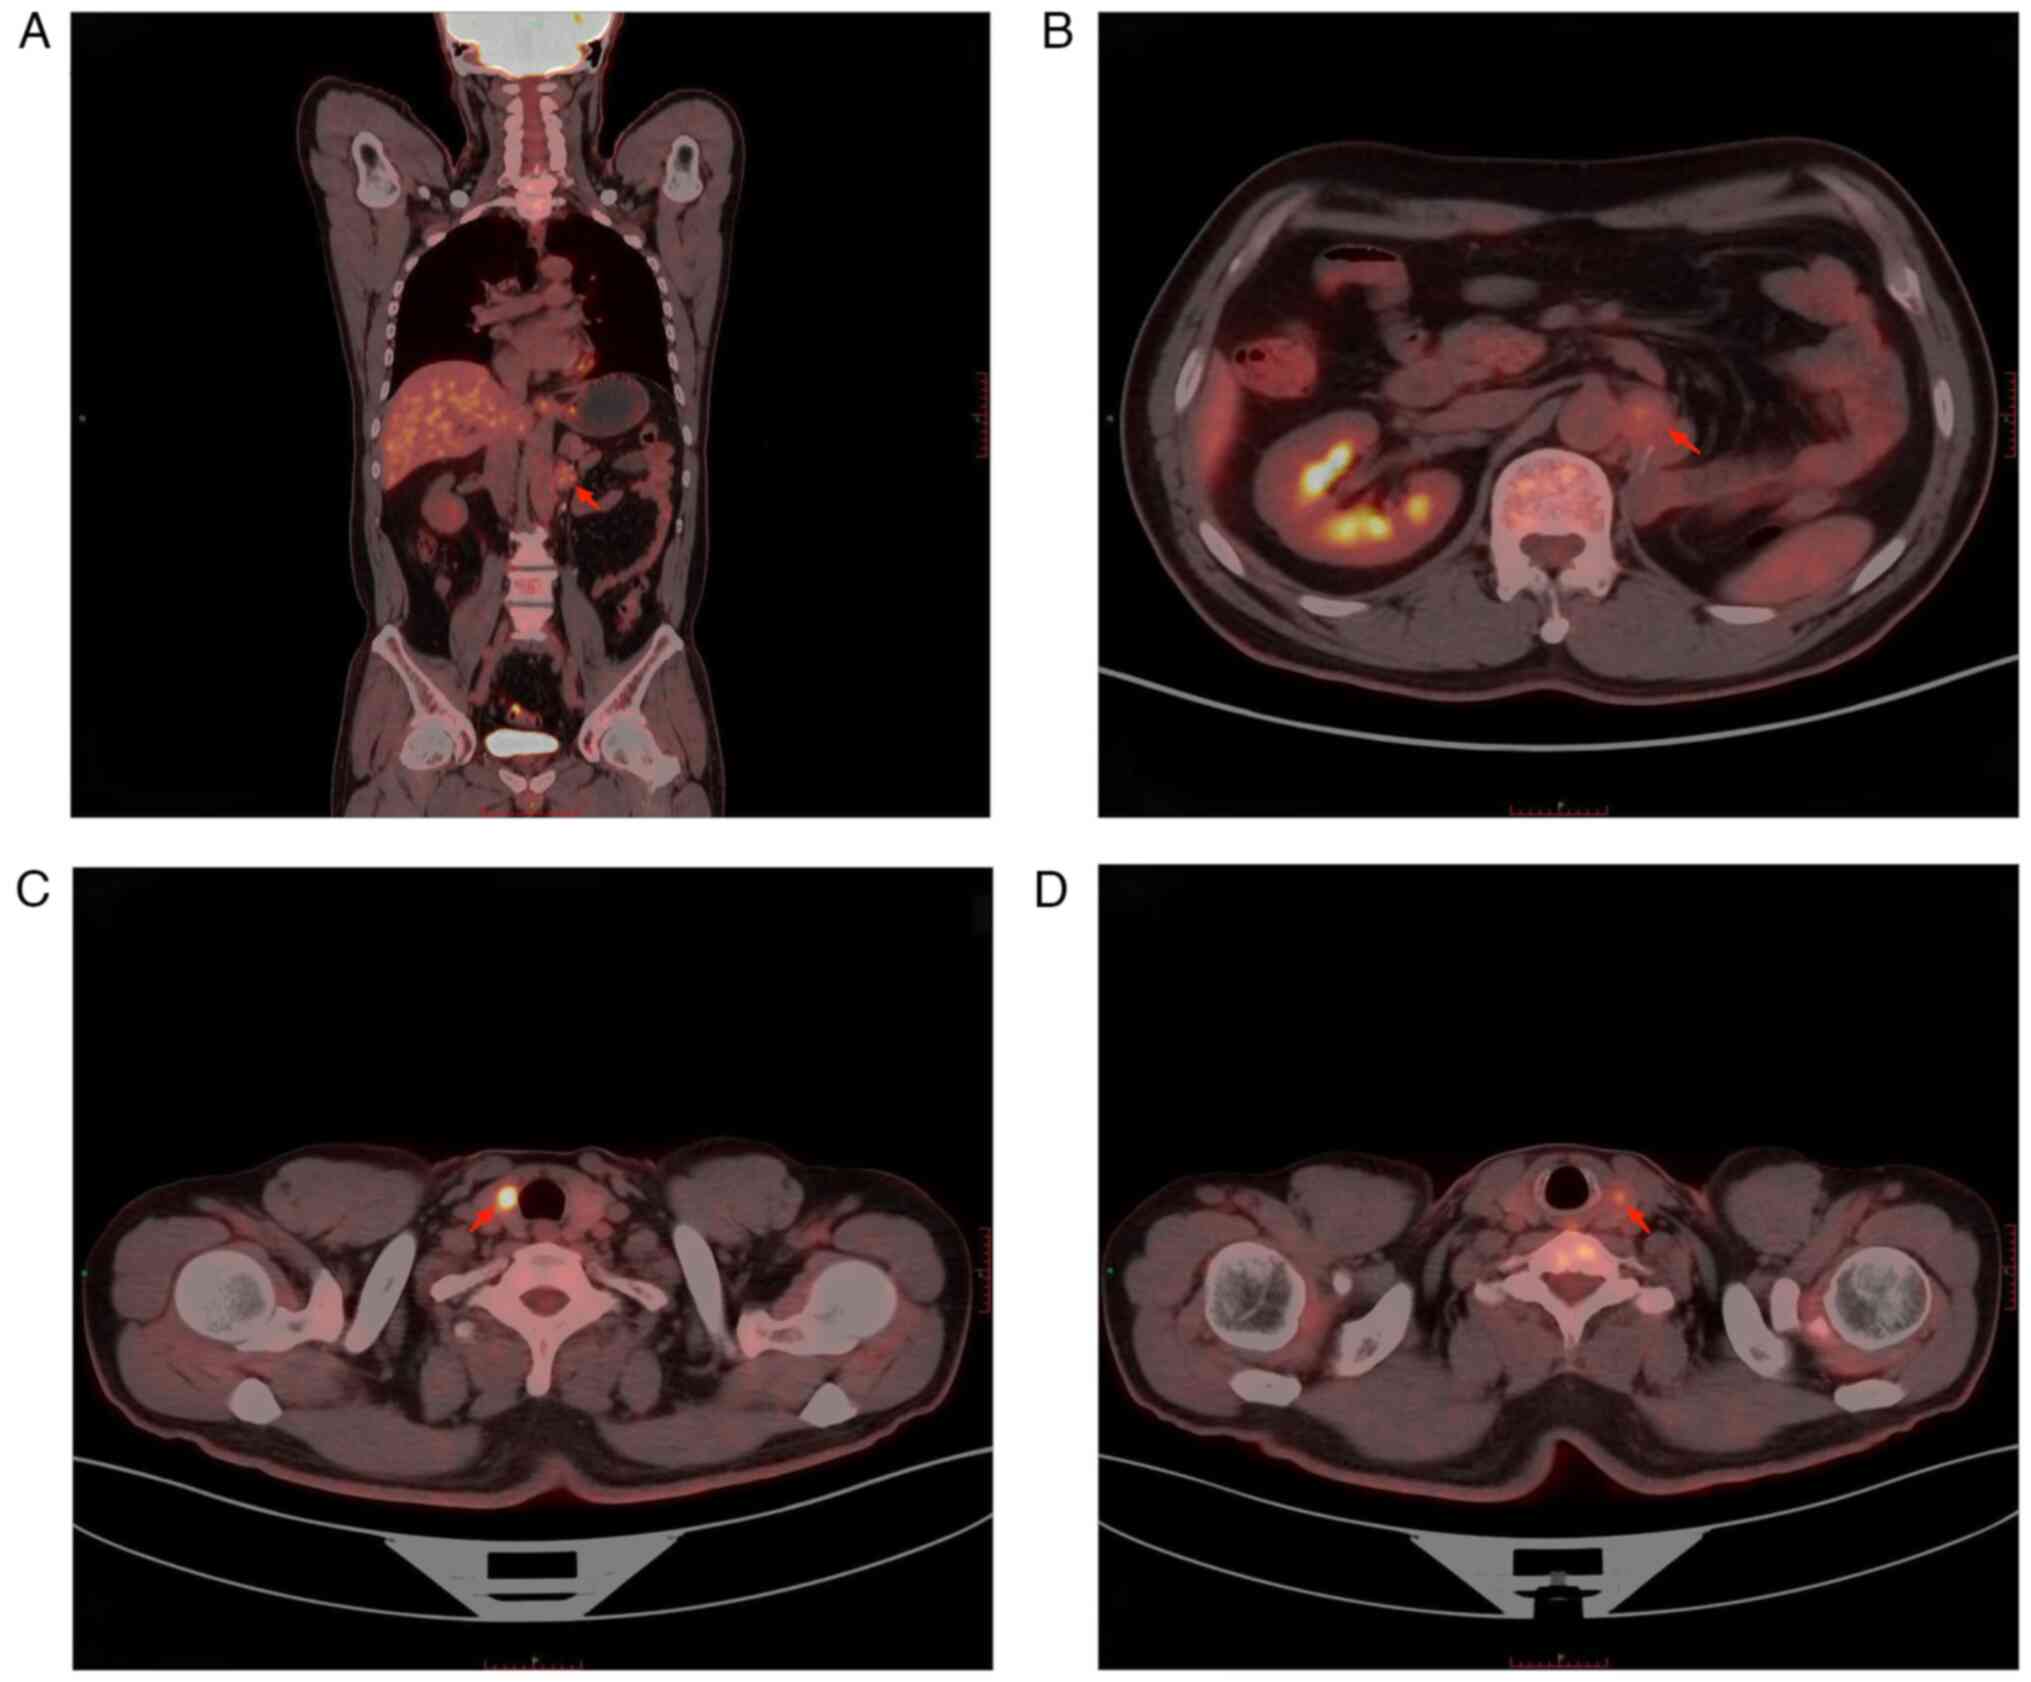

The patient was a 55-year-old male who was admitted to the Thyroid Surgery Department of The Affiliated Hospital of Southwest Medical University (Luzhou, China) in February 2022 due to the presence of thyroid nodules. In April 2018, the patient underwent radical resection of the left kidney for ccRCC at Xinqiao Hospital, Third Military Medical University (Chongqing, China). After the operation, the pathological examination results suggested the following: Renal clear cell carcinoma, pT1aN0M0, the tumor sized ~4.0×4×3.5 cm3, with no lymph node cancer metastases or distant metastasis. Therefore, the patient refused conventional adjuvant therapy after the surgery and underwent regular physical examination follow-up. In November 2021, abdominal computed tomography (CT) revealed para-aortic lymph node carcinoma metastasis (Fig. 1A), positron emission tomography (PET)-CT showed that the patient had a left para-aortic nodule after left nephrectomy and furthermore, glucose metabolism was slightly increased, and the nodule was suspected to be lymph node metastasis (Fig. 2A and B). Bilateral thyroid nodules and increased glucose metabolism were considered to indicate thyroid cancer (Fig. 2C and D), and the patient underwent laparoscopic retroperitoneal mass resection. Postoperative pathological examination suggested lymph node metastasis of ccRCC. Postoperative review via enhanced abdominal CT indicated complete resection of the retroperitoneal metastases (Fig. 1B). In November 2021, thyroid ultrasound Doppler revealed hypoechoic nodules in the left thyroid gland, resembling Chinese-Thyroid Imaging Reporting and Data System (C-TIRADS) 4C (nodule 1: Red arrow) and C-TIRADS 4B (nodule 2: Green arrow) (Fig. 3A). Of note, C-TIRADS is Chinese version of TIRADS suitable for Chinese clinical practice modified based on thyroid ultrasound data in China. The Chinese Medical Association Ultrasound Medical Expert Committee modified the data system by current TIRADS and non-TIRADS risk stratification, combined with the latest literature reported in China and worldwide, keeping in mind the national conditions (9). The cervical lymph node at level VI was enlarged with an abnormal structure, with a maximum size of 0.5×0.3 cm2. Histocytological examination performed according to standard procedures (10) by fine-needle aspiration (FNA) suggested PTC (nodule 1) (Fig. 3B). As the time interval between thyroid surgery and the previous retroperitoneal mass resection was relatively short, contrast-enhanced CT of the head, neck, chest and abdomen was performed prior to thyroid surgery and no obvious evidence of metastasis was found. Therefore, PET-CT was not performed again. However, it was recommended to the patient to repeat the PET-CT for the systemic assessment at a later follow-up visit. Based on the abovementioned examination results, papillary carcinoma of the left thyroid gland was suspected before surgery and surgical resection was performed in February 2022. During surgery, two gray hard masses sized ~0.4×0.3×0.3 cm3 (nodule 1: red arrow) and 1.3×1.3×1.2 cm3 (nodule 2: Green arrow) were found in the left thyroid gland close to the capsule, with an unclear boundary (Fig. 4), and the distance between the two tumors was ~1 cm. Intraoperative frozen section analysis showed that the nodules were neoplastic, with capsule invasion and suspected vascular invasion, and were suggestive of follicular or medullary carcinoma. Accordingly, the nature of the tumor could not be determined as PTC, follicular carcinoma or medullary carcinoma based on FNA and intraoperative frozen section analysis results of the thyroid nodule alone. According to the 2021 Chinese Society of Clinical Oncology differentiated thyroid cancer guidelines (11) and the revised American Thyroid Association guidelines for the diagnosis and treatment of medullary thyroid cancer (12), the patient then underwent total thyroidectomy and bilateral central lymph node dissection. The histopathological examination results were as follows: Left lobe thyroid tumor (two nodules), nodule 1: The nodule composed of partly follicles and partly papillary structures lined by tumor cells with enlarged, crowded and overlapping nuclei; the tumor cells showed nuclear furrows and prominent nucleoli, and certain nuclei had a ground-glass appearance (Fig. 5A); nodule 2: The tumor cells were arranged in nests and sheets, with a large volume, clear cytoplasm, round and centered nuclei and no obvious nucleoli; abundant blood vessels were seen in the background of the tumor (Fig. 5B); follicular adenoma of the right lobe of the thyroid and reactive hyperplasia of bilateral central lymph nodes were observed. Immunohistochemistry (dewaxing of paraffin sections using xylene and descending ethanol 5 min → 100% ethanol 5 min → 90% ethanol 5 min → 80% ethanol 5 min 70% ethanol 5 min → PBS buffer rinse three times, 5 min each time. 2. Antigen repair: EDTA repair solution (PH=9.0), high-pressure repair, and steam was added for 6 min; Citric acid buffer (PH=6.0) was used for repair under high pressure, and steam was added for 3 min. The sample was naturally cooled to room temperature. 3. Further, 3.3% methanol H2O2 was soaked for 10 min to eliminate the endogenous peroxidase activity, and PBS buffer was used to rinse three times (3 min each time). 4. The primary antibody was added and incubated at 37°C for 60 min; followed by washing with PBS three times, each time for 3 min. The secondary antibody (MaxVision™ 2/HRP) was then added and incubates at 37°C for 30 min; followed by washing with PBS three times, each time for 3 min. DAB color development was performed at room temperature for 0.5–1 min; the process was controlled using a microscope, and the sample was washed with tap water to stop color development. 7. Rinsing with running water for 5 min. 8. Re-staining with hematoxylin for 2 min. 9. Further, differentiation was performed using 0.1% diluted hydrochloric acid, and saturated lithium carbonate turned blue. 10. Dehydration, transparency, and sealing: 95% ethanol (l) 1 min → 95% ethanol (l) 5 min → 100% ethanol (l) 5 min → 100% ethanol (II) 5 min → xylene 2 min → neutral gum resin sealing.) revealed the following: Nodule 1: The tumor cell component was immunoreactive to thyroglobulin (TG), thyroid transcription factor-1 (TTF-1), cytokeratin 19 (CK19) and galectin-3 (Fig. 6A-D), but common acute lymphocyte leukemia antigen (CD10) and renal cell carcinoma marker (RCC) staining were negative (data not shown). Nodule 2: The clear cell component showed immunopositivity for CD10, paired box gene 8 (PAX8) and RCC (Fig. 7A-C), but TG and TTF-1 staining were negative (data not shown). In brief, consecutive parallel sections were stained with the following antibodies according to the manufacturers' recommendations: TG (cat. no. MAB-0797), TTF-1 (mouse anti-human mAb; cat. no. MAB-0677; Maixin Fuzhou), CK19 (mouse anti-human mAb; cat. no. MAB-0829), galectin-3 (cat. no. MAB-0835; Maixin Fuzhou), CD10 (cat. no.MAB-0668), PAX8 (cat. no. MAB-0837; Maixin Fuzhou), RCC (all mouse anti-human mAb; cat. no. MAB-0309; all Maixin Fuzhou). The secondary antibody was MaxVision™ 2 plus polymer HRP (mouse/rabbit) IHC Kit (cat. no. KIT-5930; Maixin Fuzhou). However, the absence of quantitative results for these experiments is a limitation of the present study. On postoperative day 1, the parathyroid hormone level was 5.14 pg/ml (reference range, 8.7–79.6 pg/ml) and the blood calcium concentration was 1.98 mmol/l (reference range, 2.11–2.52 mmol/l). The patient presented with fingertip and perioral numbness, which may be caused by transient hypocalcemia resulting from impaired parathyroid blood supply. Treatment with calcium supplementation was provided, and the parathyroid hormone and blood calcium concentration were reexamined on postoperative day 3. The parathyroid hormone levels were 10.4 pg/ml and the blood calcium concentration was 2.36 mmol/l. The patient did not show any hypocalcemia again. Levothyroxine (100 mg qd) was administered on postoperative day 2. Following thyroid surgery, multidisciplinary consultations were acquired from the Departments of Urology, Oncology and Thyroid Surgery, and other disciplines. This patient had undergone surgical resection and was treated with sunitinib (50 mg qd) for 2 cycles (taking sunitinib for four weeks per cycle followed by a two-week interval). The patient was followed up for 14 months and followed a good diet and having a good sleep, and normal thyroid function and no new metastasis was observed. Hereafter, the patient will be followed up every 3 months and the results will be reported.

Figure 2.

Positron emission tomography-computed tomography in November 2021. (A) Coronal section demonstrated that the left kidney and left adrenal gland are not shown. A soft tissue density nodule (red arrow) is seen on the left side of the abdominal aorta and there were no swollen lymph nodes in the remaining pelvic abdominal cavity. (B) Transverse sections demonstrated that a soft tissue density nodule of ~2.3×2.0 cm2 in size (red arrow) on the left side of the abdominal aorta. The margin of the nodule are poorly demarcated with the left crus of the diaphragm. The imaging agent intake increased unevenly. SUVMAX was ~3.1. (C) Nodule of the right lobe of the thyroid (red arrow): Poorly defined border, significantly increased imaging agent uptake, SUVMAX of ~12.2. (D) Nodule of the left lobe of the thyroid (red arrow): Border clear, slightly increased imaging agent uptake and SUVMAX of ~3.1. SUVMAX, maximum standard uptake values at the PET scan.